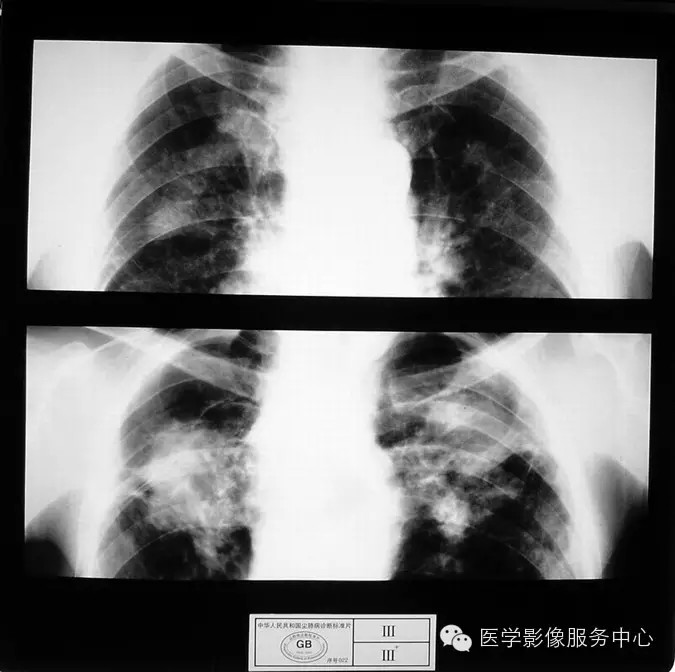

4.4 三期尘肺(Ⅲ)

a)Ⅲ:有大阴影出现,其长径不小于20mm,短径不小于10mm。

b)Ⅲ :单个大阴影的面积或多个大阴影面积的总和超过右上肺区面积者。